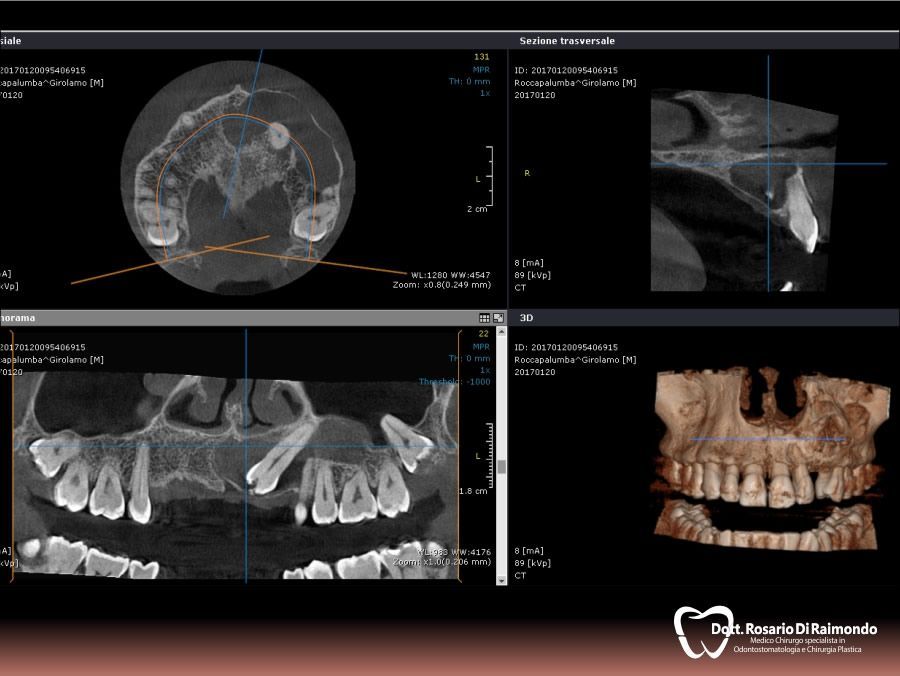

Cisti

La cisti è una formazione patologica che presenta una forma generalmente sferica ed ha la tendenza ad un lento accrescimento asintomatico a spese dei tessuti circostanti.

L'aumento di volume di una cisti può portare al riassorbimento delle radici di denti contigui e dei tessuti ossei che la contengono. In altre occasioni si può verificare la dislocazione degli elementi dentali adiacenti.

La posizione e la velocità di crescita di una cisti sono due dei fattori che il dentista prende in considerazione nel decidere se procedere alla rimozione chirurgica della stessa o monitorarla nel tempo tramite controlli clinici e radiografici periodici.

Casi Trattati

Di seguito riportiamo alcune fotografie di casi esplicativi di Chirurgia Orale.